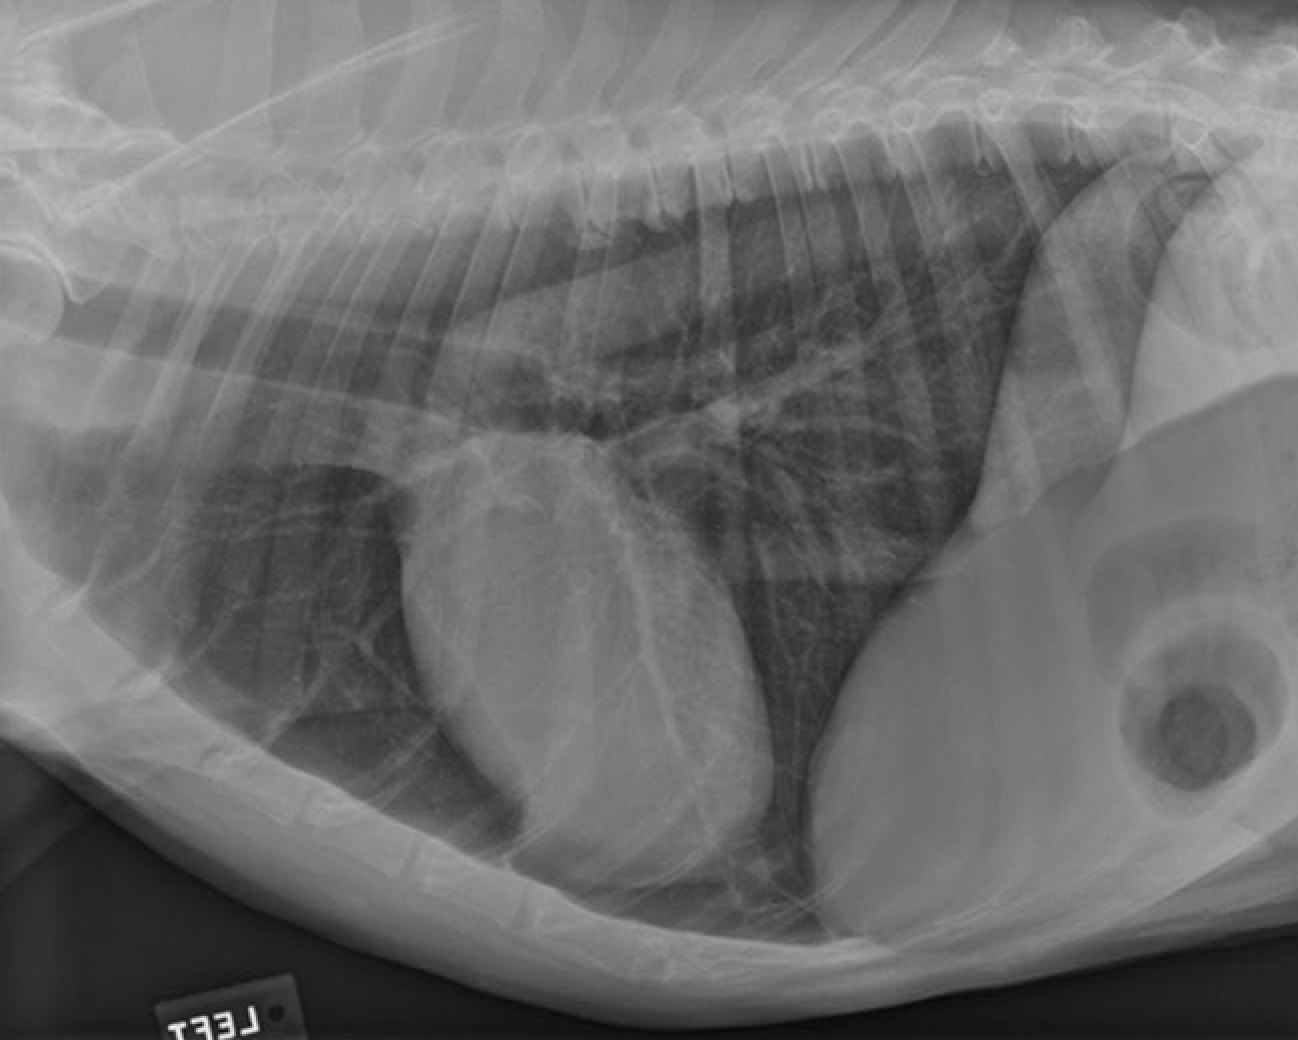

identify the structures of the cat thorax

A= heart

B= diaphragm

C= liver

how does the shape of the cat thorax differ than the dogs

shape: narrow and steep, heart sits more at an angle and it is positioned more caudally (4th-7th intercostal space) also little of the heart is covered by the forelimb as the triceps reaches no further than the 4th rib

Identify Manubrium of sternum, First rib, Apex of heart, Base of heart, Diaphragm and First lumbar vertebra

Again note the shape of thoracic cavity. How does it compare to that of the dog?

Narrower particularly about the thoracic inlet